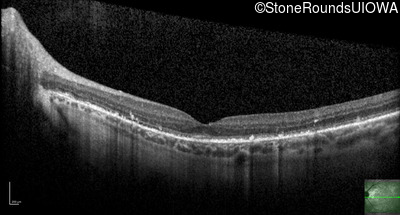

Optical Coherence Tomography - Right - 20/20 -1

Exemplar / OCT Stack

OCT Stack